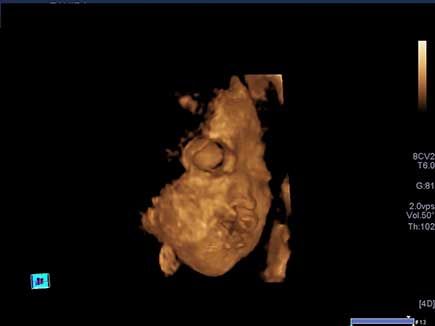

Challenge your diagnostic skills: See anything out of the ordinary in the kidneys of this third trimester fetus?

Challenge your diagnostic skills: See anything out of the ordinary in this second trimester fetal heart study?